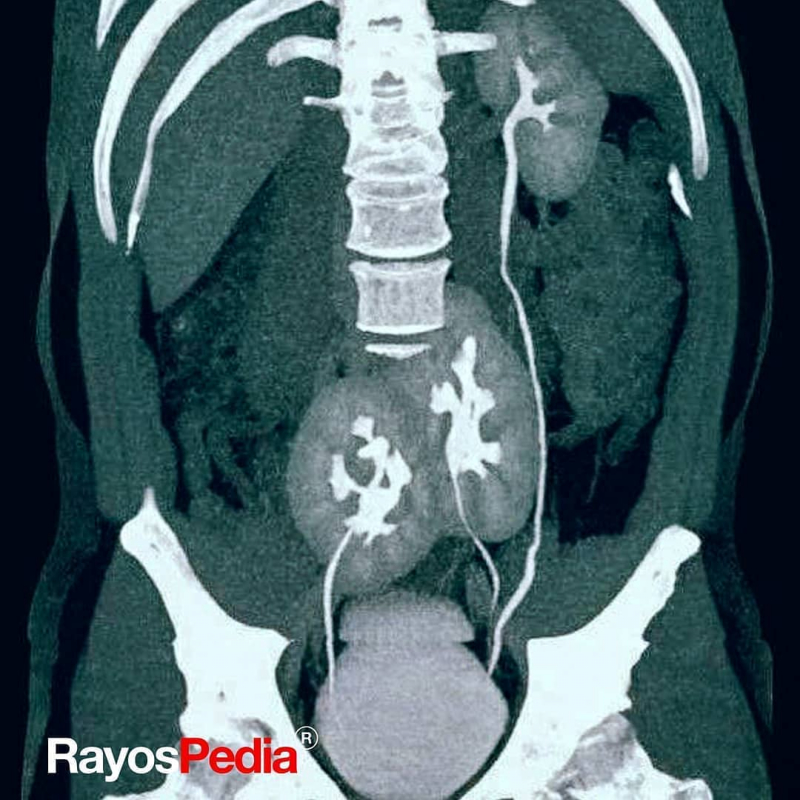

Radiografía de una persona con 3 riñones.